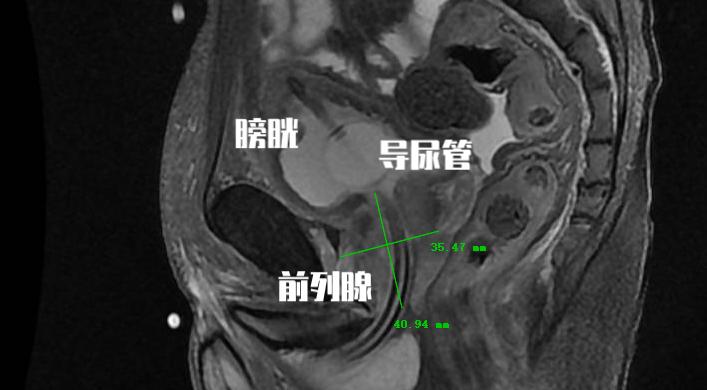

前列腺增生顾名思义就是前列腺的体积增加,这是前列腺增生在解剖学上的表现之一。一般我们将患者初次就诊的前列腺体积定义为基线。 研究证实基线前列腺体积与前列腺增生临床进展显著相关。 大部分的研究都将这个 体积定义在30ml(前列腺体积=0.52*左右径*前后径*上下径)。前列腺体积超过30ml的患者需要药物或手术治疗的可能性将提高4倍!

前列腺增生临床进展危险因素四:前列腺膀胱内突出度

这是一个彩超检查经常会报的指标,但是往往会被患者和医生所忽视。 前列腺膀胱内突出度是超声测得的前列腺矢状面下突入膀胱内的前列腺尖端至膀胱与前列腺交界平面的距离。 这是用于预测膀胱出口梗阻的重要指标。 这个突出程度越重,患者往往临床症状越重,同时需要手术治疗的可能性也越高!